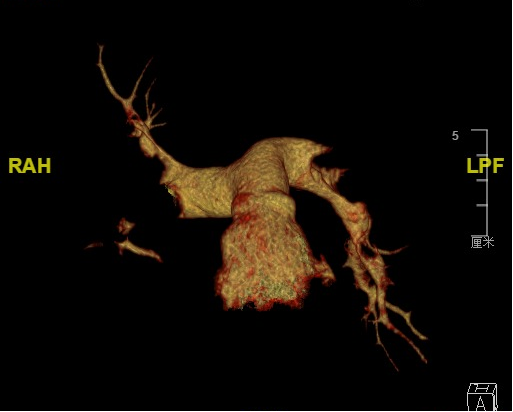

术前分析:

该患者是一名52岁中年男性,10天前无明显诱因突发短暂性意识不清,并持续头晕、胸闷、气促。BNP 2223 pg/ml、DDimer˃4.00 ug/ml;

术前CTA影像

血管外科团队充分评估,认为应用新型经导管肺动脉取栓系统是更优的治疗方式。